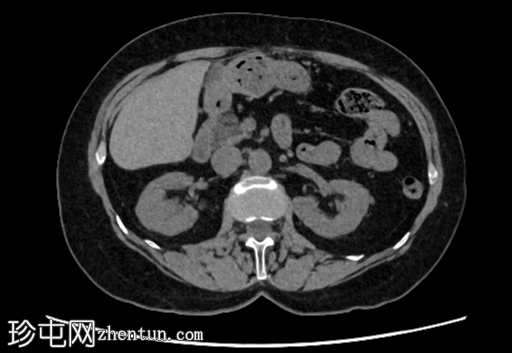

轴位增强扫描(门静脉期)

2.png

右肾后上极可见2.8 cm外生性强化病灶,提示肾细胞癌(RCC)。右肾静脉和下腔静脉通畅。未见明显局部淋巴结肿大。右肝叶可见高密度金属影。可见含脂肪的脐疝。